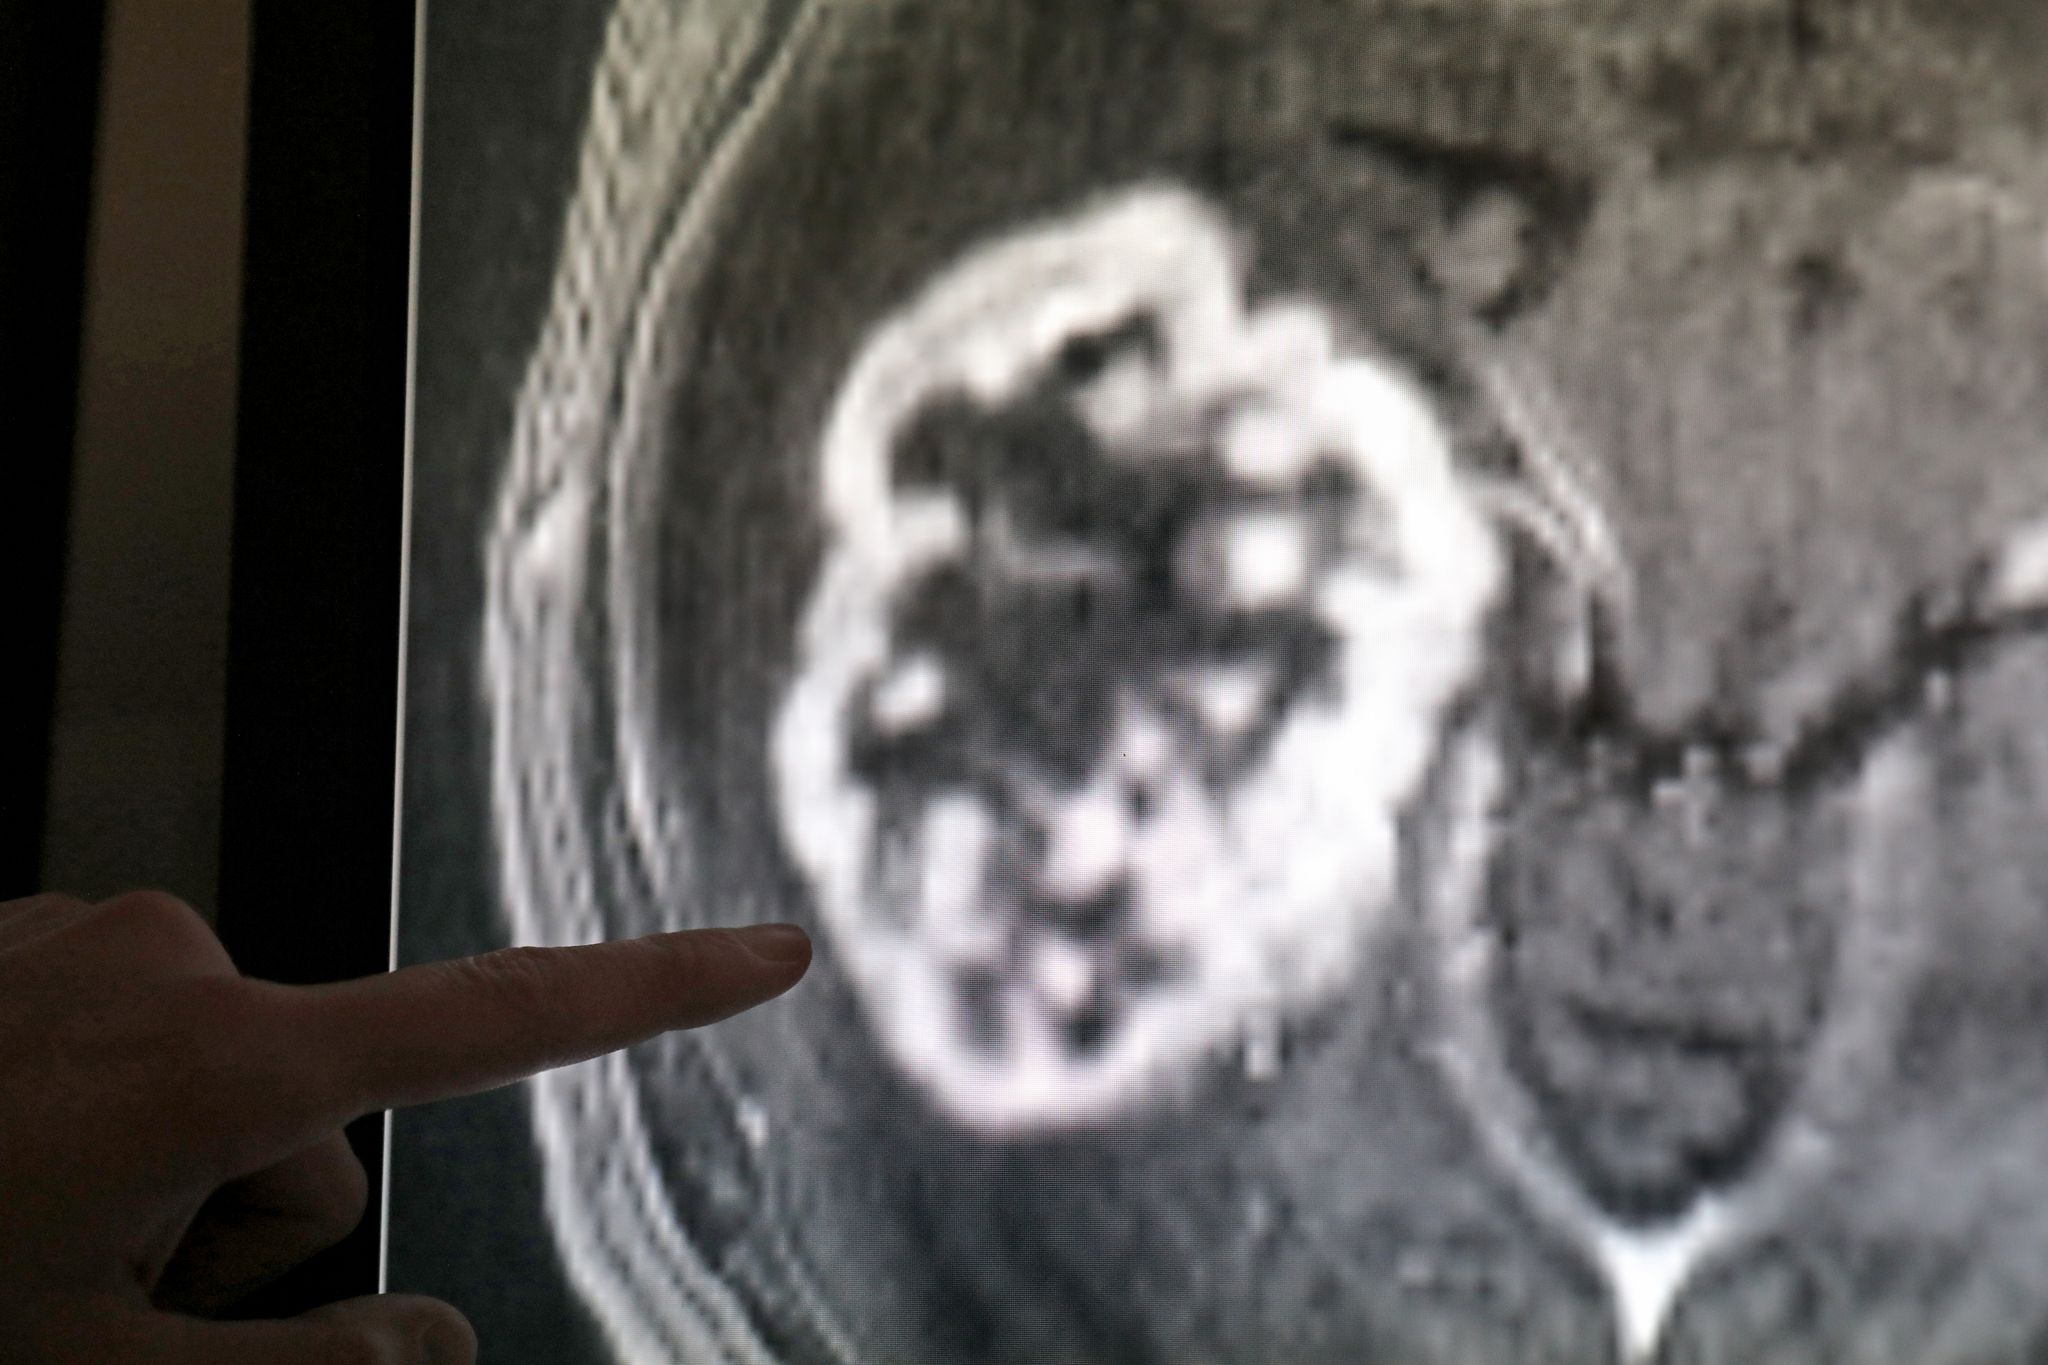

Veštačka inteligencija (AI) u onkologiji i inovativne metode lečenja su u fokusu zdravstvenog kongresa Yes!con koji počinje u petak u Berlinu.